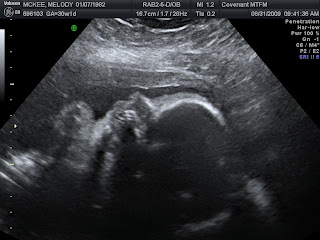

So...here's my fat baby at 30 weeks 1 day :)